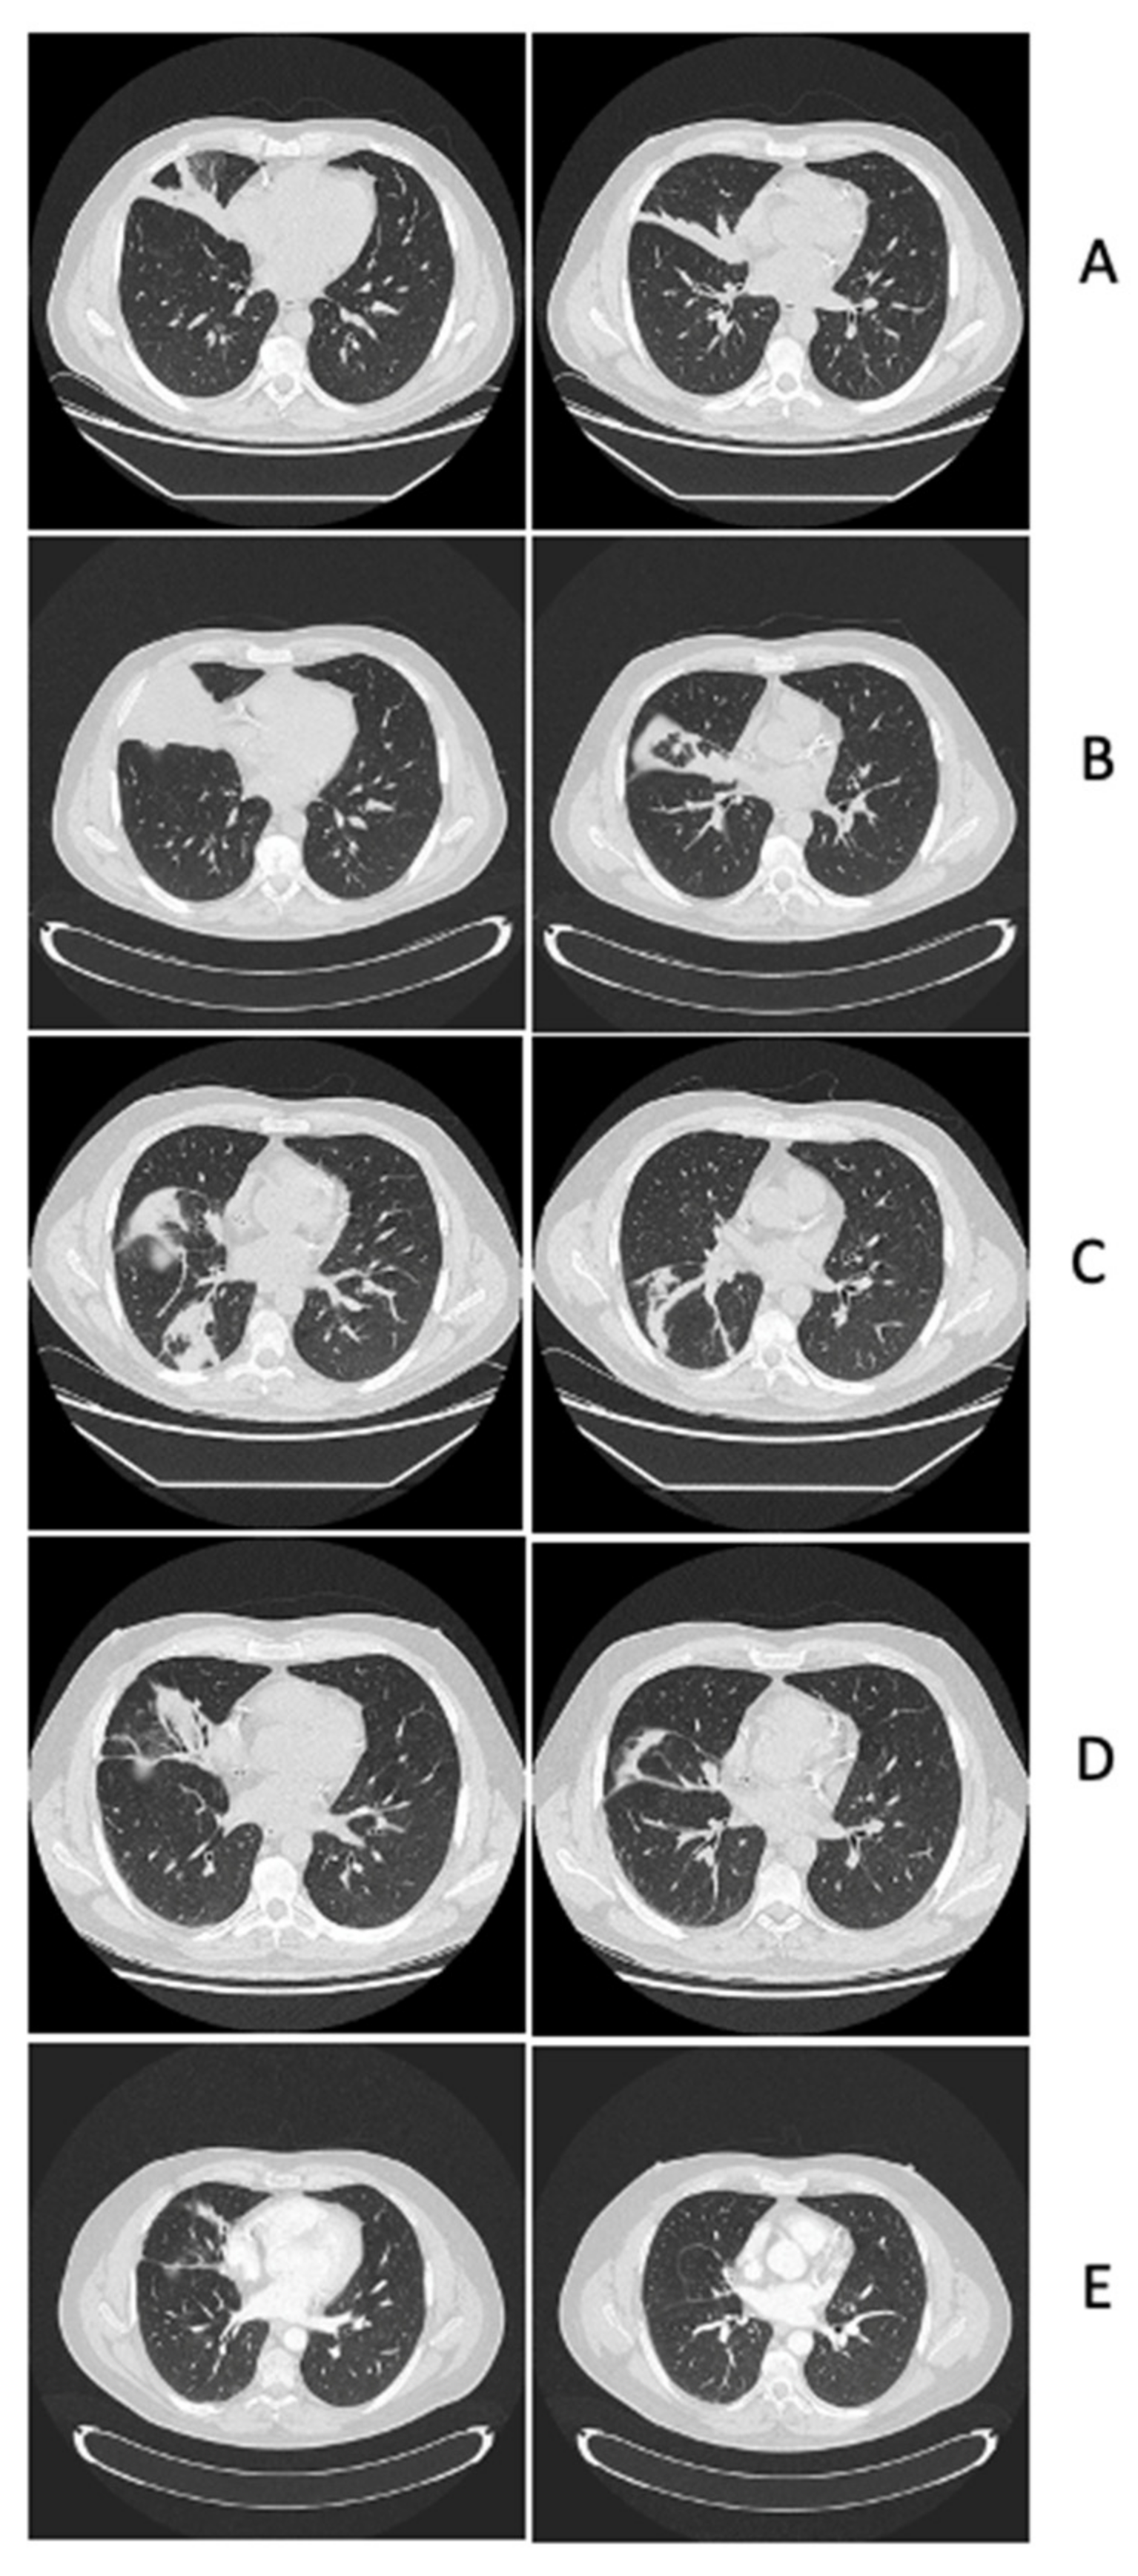

2.1. Leukaemia Diagnosis, Infectious Complications of Remission Induction and Consolidation Chemo-Therapies, Diagnosis and Management of Central Nervous System Lesions

2.1.1. Case Presentation

2.1.2. Case Discussion and Literature Review